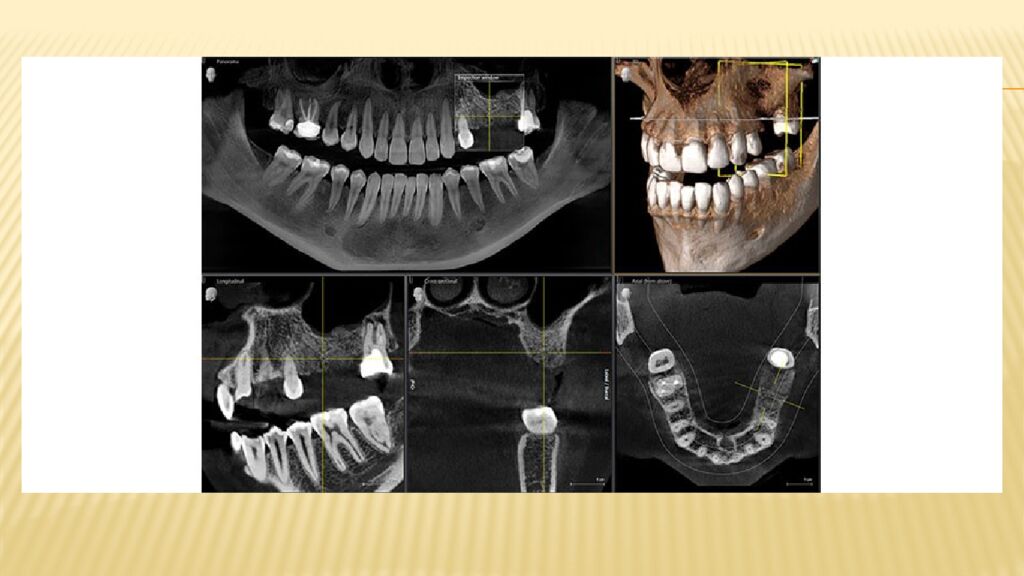

• КЛКТ кезінде алынатын суреттер

Конусты-сәулелі компьютерлік томография (КЛКТ) Бұл зерттеу алынатын сәулеленудің ең төменгі дозасымен сипатталады, әрі түсірілім дәстүрлі рентгендік аппаратпен жүргізілетін тексеріспен салыстырғанда анағұрлым ақпаратты болып шығады. Жақ сүйектерінің КЛКТ- сы (конус- сәулелі компьютерлік томография) жақ -бет аймағын зерттеуге қолданылатын көлемді сандық зерттеулер қатарына жатады. Үшөлшемді бейнелер арнайы бағдарламалық қосымшалардың көмегімен алынады. Бейнелердің сапасы жоғары болуы үшін пациент процедура бойы толық қимылсыз қалуы тиіс. Басты иммобилизациялау құралдары арқылы белгілі бір қалыпта бекіткеннен кейін, конус- сәулелі компьютерлік томограф оның айналасында айналмалы қозғалыс жасайды. Аппараттың бір жағында рентген сәулесінің көзі, екінші жағында – қабылдағыш орналасады. Томограф компьютерге қосылады және барлық алынған ақпарат сол жерде өңделеді.

Тексеру барысында аппарат зерттелетін аймақтың жалпы жағдайын көрсететін көптеген түсірілім жасайды. Бұл суреттердің диагностикалық құндылығы болуы үшін маман оларды арнайы бағдарламалар арқылы өңдейді. Бұл қажетті аймақты әртүрлі проекцияларда қарауға, тіндердің құрылымдарын өлшеуге, сондай-ақ диагноз қоюмен айналысатын бейінді маманға арналған үшөлшемді модель құруға мүмкіндік береді. Мысал ретінде суретте көруге болатындар тізімі : Тісті қоршаған жұмсақ тіндердің жағдайы. Сүйек тіндерінің құрылымдық патологиялары : атрофия, остеопороз, остеонекроз және т.б. Сүйек құрылымдарының патологиялық өзгерістері. Түсірілімдерде үзіктер, талшықтану және басқа да жағымсыз процестер анық көрінеді. Тіс түбірі өзектерінің жағдайын талдау. Тіс қаптамаларының ( коронкалардың ) ақаулары және тағы басқалар.